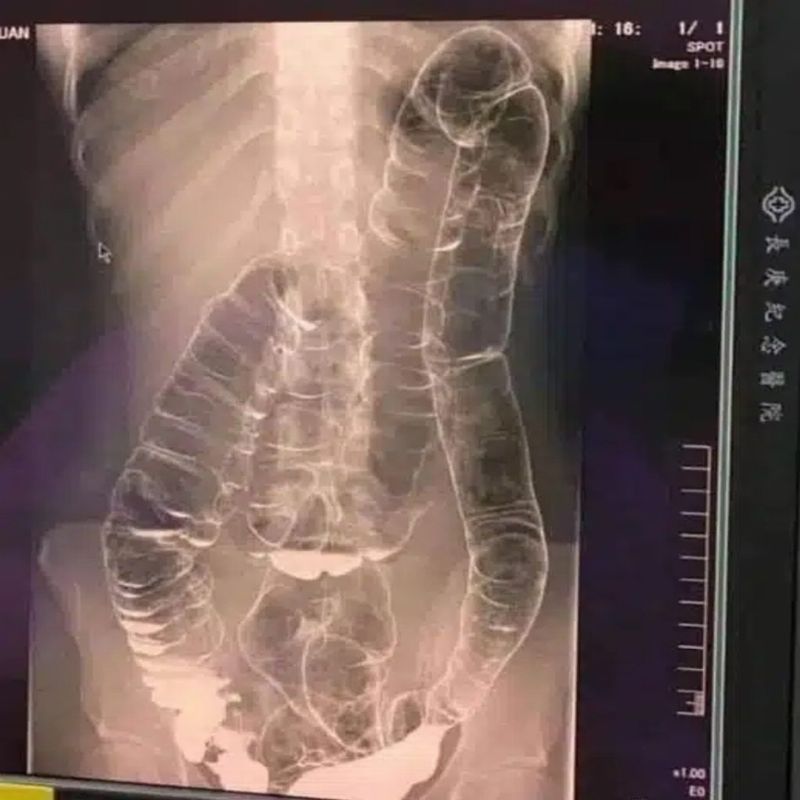

Cólon saturado: quando o corpo dá sinais de alerta

A constipação, ou intestino preso, é um problema que afeta milhões de pessoas.